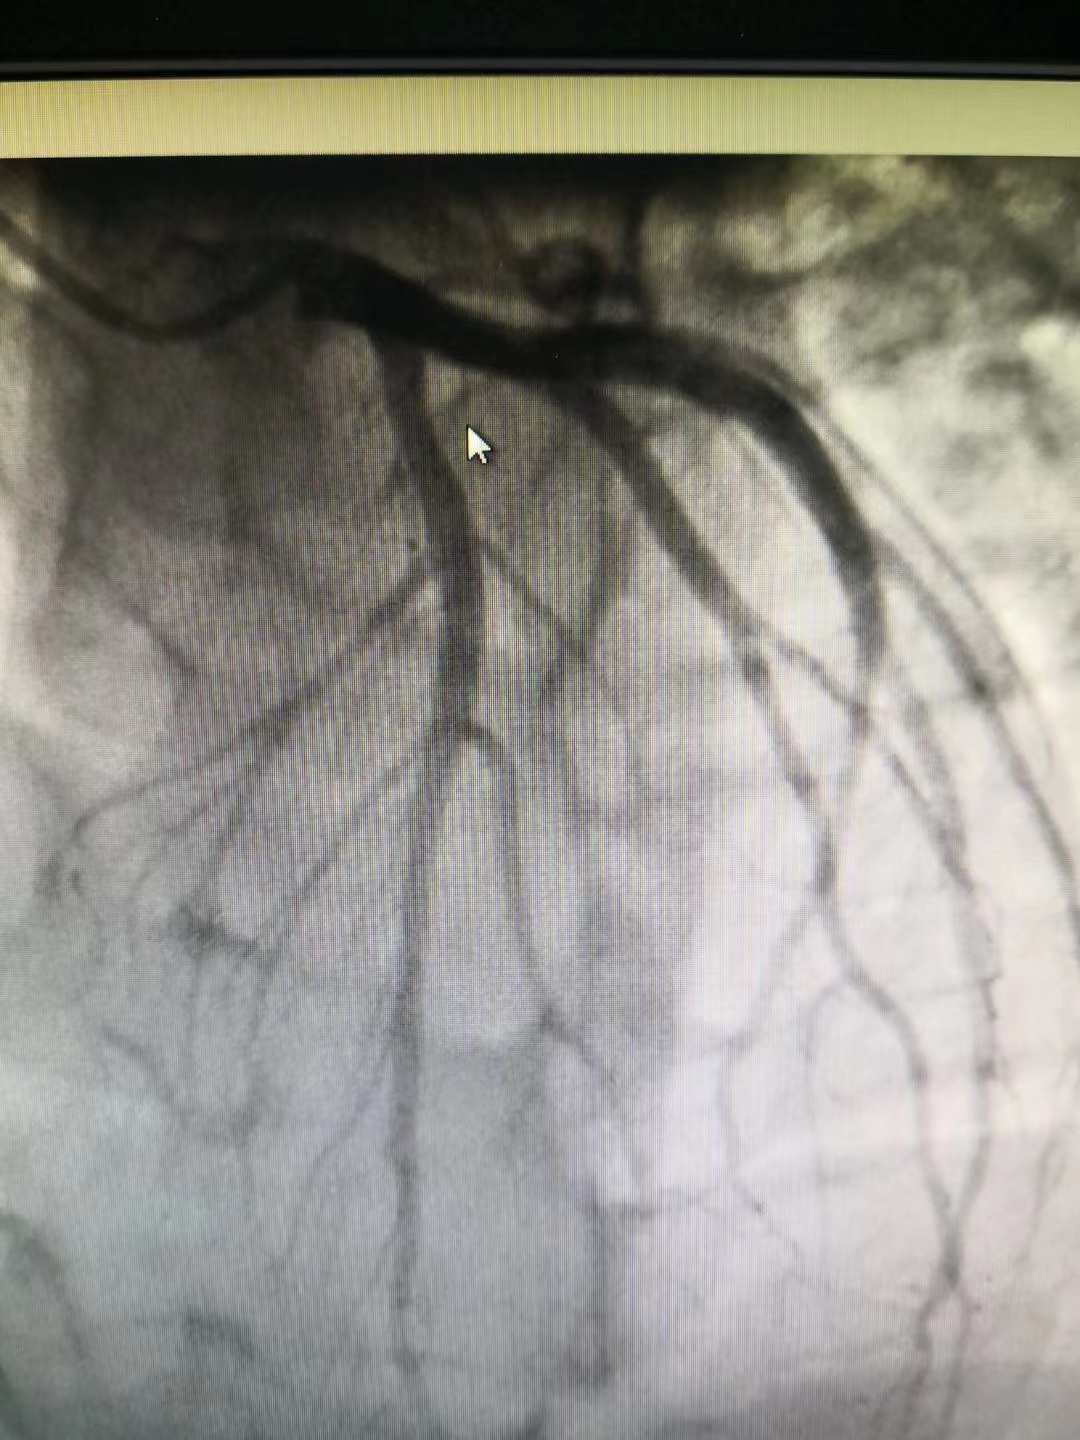

冠脈造影提示前降支近段50%局限性狹窄,遠(yuǎn)端肌橋

小貼士:冠狀動脈造影(CAG)

冠狀動脈造影(CAG)是一項(xiàng)用于檢查動脈血管是否正常的輔助檢查,是診斷冠心病的有效方法之一。將導(dǎo)管經(jīng)大腿股動脈或其它周圍動脈插入送至升主動脈,再插入左或右冠狀動脈口,注入造影劑,使冠狀動脈顯影。CAG能較明確地揭示冠狀動脈的解剖畸形及其阻塞性病變的位置、程度與范圍,是目前唯一能直接觀察冠狀動脈形態(tài)的論斷方法,醫(yī)學(xué)界稱其為“金標(biāo)準(zhǔn)”。